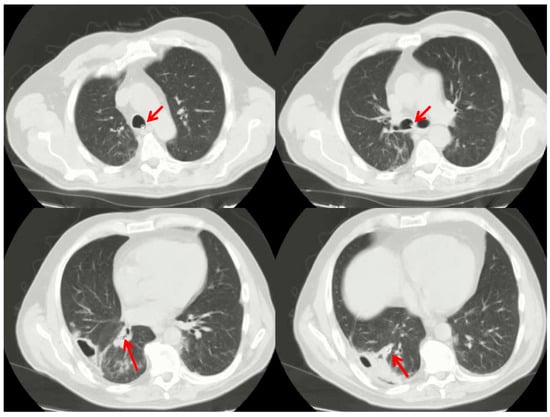

Endoscopic Treatment and Pulmonary Rehabilitation for Management of Lung Abscess in Elderly Lymphoma Patients